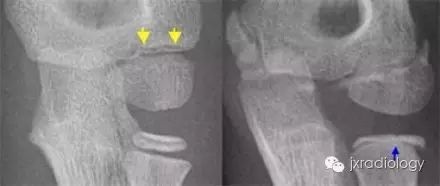

骨骺裂必须和骨折鉴别。一般骨折损伤2-3周后复查平片可见愈合的迹象。识别这个现象是重要的,以避免过度治疗和不必要的手术干预。

骨骺裂必须与骨折相鉴别。通常,如果在受伤后 2-3 周重复 X 线检查,骨折就会显示出愈合迹象。识别该实体对于避免过度治疗和不必要的手术干预非常重要。骨骺裂意译为骨骺裂,结合临床病史及复查才能和骨折区分。

黄箭骨折;蓝箭是骨骺裂。留下轻微的外侧髁骨折。位移小于 2 毫米,可能很稳定。对一个不同的案例。倾斜的视图给人留下了断裂的良好印象。蓝色箭头表示桡骨骺裂(正常变异型)